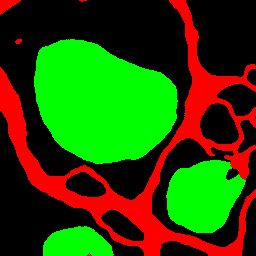

Drosophila cell image [6] consists of 20 images including 4 classes of cell membrane, cytoplasm, mitochondria, and synapses with an image size of 1024×1024102410241024\times 1024 pixels. In experiment, we divided the images into 12 training images, 3 validation images, and 5 test images, and divided the original image size into 16 regions of 256×256256256256\times 256 pixels without overlap. The final number of images was 192 for training, 48 for validation, and 60 for evaluation. The batch size is set to 4 for training. In the segmentation images, red indicates cell membrane, black indicates cell membrane, green indicates mitochondria, and blue indicates synapses.

Figure 6: Segmentation results on Drosophila dataset

4.3.2 Results on Drosophila Cell Images

As shown in Table 3, the proposed method improved the accuracy compared to the conventional methods in many classes. In particular, our proposed AML-Net and Top-Down PDA-Module improved the accuracy of synapses, which is the most difficult class. Top-Down PDA-Module is a top-down attention mechanism using ground-truth, and it is considered that the accuracy is improved due to its ability to create attention maps that explicitly strengthen particularly difficult synapses. In addition, the accuracy of ATA-Module was improved in many classes compared to conventional methods. From the feature maps obtained from the discriminator, it can be concluded that the ATA-Module contributes to the accuracy improvement because the similarity between pixels is appropriately enhanced by the ATA-Module. Therefore, AML-Net with the appropriate combination of Top-Down PDA-Module and ATA-Module can improve the accuracy of IoU for many classes. Deeplabv3+ with ResNet-50 as its backbone does not train well on Drosophila cell images, indicating that even successful models for scene segmentation are not effective for cell image segmentation. In addition, AML-Net has better IoU accuracy than FastFCN using ResNet-50.

The top image group in Figure 6 shows that Top-Down PDA-Module and AML-Net can accurately detect synapses that are easily over-detected by conventional methods. However, our method also caused excessive false positives for cell membrane and mitochondria on the right side. The false positives were probably caused by the fact that the input image shows something very similar to cell membrane and mitochondria. In the lower group of images, U-Net and Top-Down PDA-Module fail to detect mitochondria, and misidentify them as mitochondria in some cell membranes, while ATA-Module and AML-Net correctly identify mitochondria, reducing the number of undetected or false positives. Thus, we can see that AML-Net is able to recognize mitochondria by utilizing the advantages of both ATA-Module and Top-Down PDA-Module.